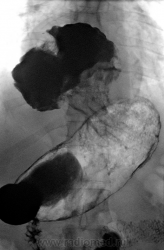

Пациент 37 лет без жалоб, был направлен на R-скопию пищевода и  желудка после проведения МСКТ-абдоминального:

А вот еще по данным КТ-сканам четко видно фиксированную грыжу пищеводного отверстия диафрагмы: